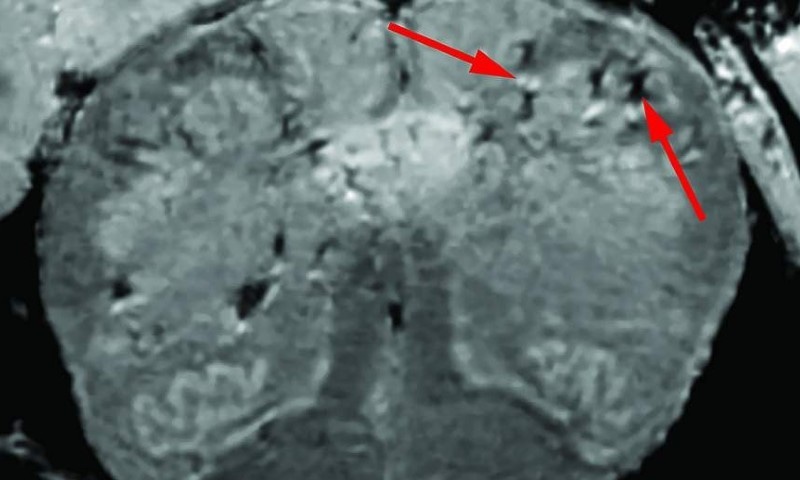

ماہرین نے خصوصی اسکینرز کی مدد سے ہلاک مریضوں کے دل اور انس کو کنٹرول کرنے والے دماغی حصوں کے خلیات کا معائنہ کیا جو کورونا سے سب سے زیادہ متاثر ہونے والے دماغی حصے سمجھے جاتے ہیں، اس دوران محققین نے خلیات میں جگمگاتے نشان دیکھے، مذکورہ روشن ہونے والی جگہ پر ایسی خون کی شریانیں تھیں جو معمول سے زیادہ پتلی ہوتی ہیں اور کئی بار ان سے بلڈ پروٹین دماغ میں لیک ہوتے ہیں، یہ سلسلہ ممکنہ طور پر وائرس کے نتیجے میں پیدا ہوتا ہے۔

اس کے نتیجے میں مدافعتی ردعمل متحرک ہوتا ہے لیکن دماغی خلیات کے وہ حصے جو تاریک تھے وہاں مدافعی ردعمل نہیں دیکھا گیا البتہ محققین نے وائرس کے کوئی آثار دماغی ٹشوز کے نمونوں میں دریافت نہیں کیے۔